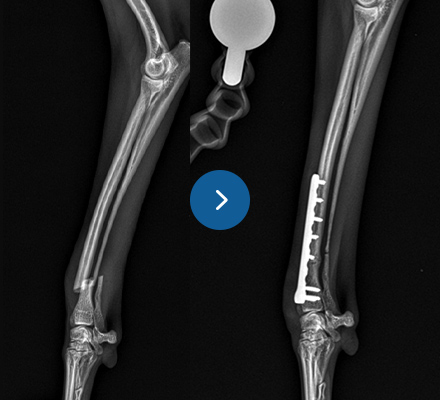

십자인대 질환

- TPLO

- 9살, 11kg, 아메리칸코커스패니엘

십자인대 질환에 대해 TPLO 수술을 진행하였습니다. 수술 직후 방사선에서 절골선이 보이지 않습니다.

정교하고 안정적인 수술로 다음날부터 산책이 가능합니다.

십자인대 질환

- 5 hole TPLO

- 11살 3kg 말티즈

다양한 회사의 플레이트 제품을 가지고 있어서 환자 맞춤으로 수술이 가능합니다.

일반적으로 TPLO 수술 시 6홀 플레이트를 사용하는데

이 환자의 경우 뼈가 작아 5홀 플레이트를 사용하여 교정하였습니다.

골절수술

- 요척골 단순골절

- 4살, 이탈리안그레이하운드

고난이도 상완골 원위부 골절

- IOHC, 상완골과골절

- 4개월 시추 2.6kg